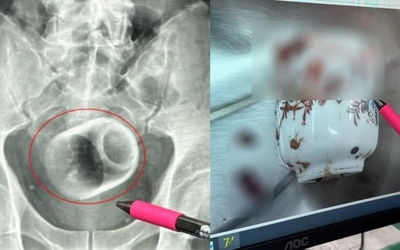

Đi khám vì tiểu máu, người đàn ông 40 tuổi tá hoả khi phát hiện mắc hội chứng "bụng quả mận khô"

Một bệnh nhân nam 40 tuổi nhập viện vì tiểu máu và đau thắt lưng đã được chẩn đoán mắc hội chứng Prune Belly (Eagle–Barrett), một dị tật bẩm sinh cực hiếm, thường phát hiện ở trẻ sơ sinh.